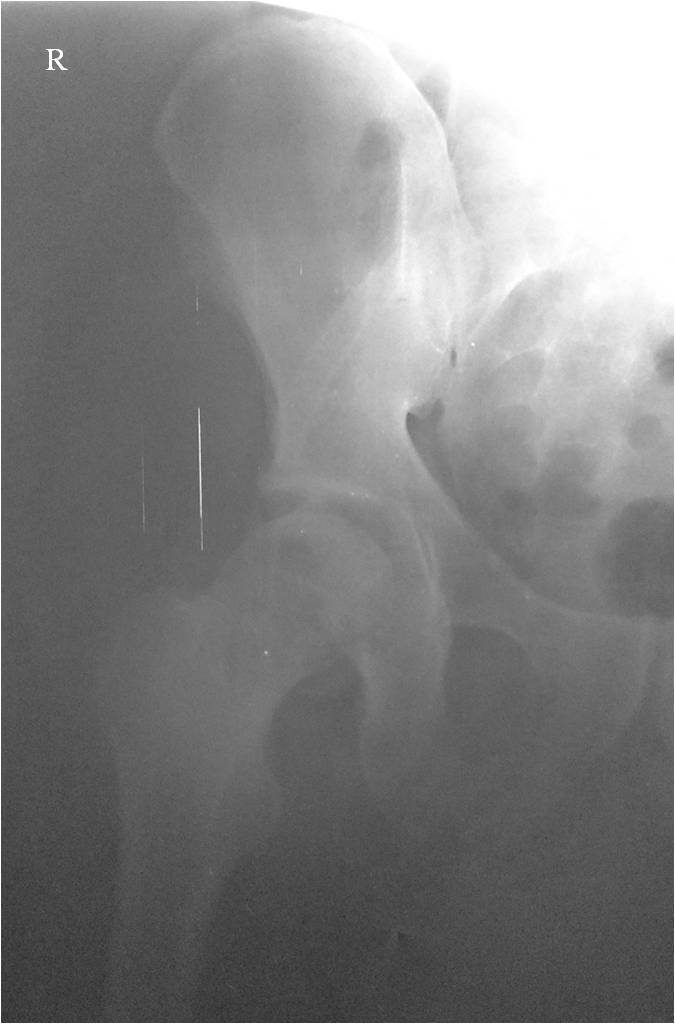

Уважаемые коллеги! Всех с наступившим 2015 годом, всем здоровья и мирного неба над головой! Мужчина, 46 лет, пострадал в результате ДТП (водитель). Удар пришелся через согнутое правое колено об приборную панель, что привело к заднему вывиху головки бедра. При госпитализации кроме вывиха бедра диагностирован перелом нижнего сегмента головки бедра и закрытый перелом с/3 правого плеча (АО 12-В2).

При поступлении выполнено закрытое вправление головки бедра, налажено скелетное вытяжение. Контрольный рентген показал разницу в ширине суставных щелей в сравнении с неповрежденной стороной. Сделали КТ, которое подтвердило наличие внутрисуставного фрагмента задней стенки вертлужной впадины и перелом нижне-медиального сегмента головки со смещением (Pipkin IV).